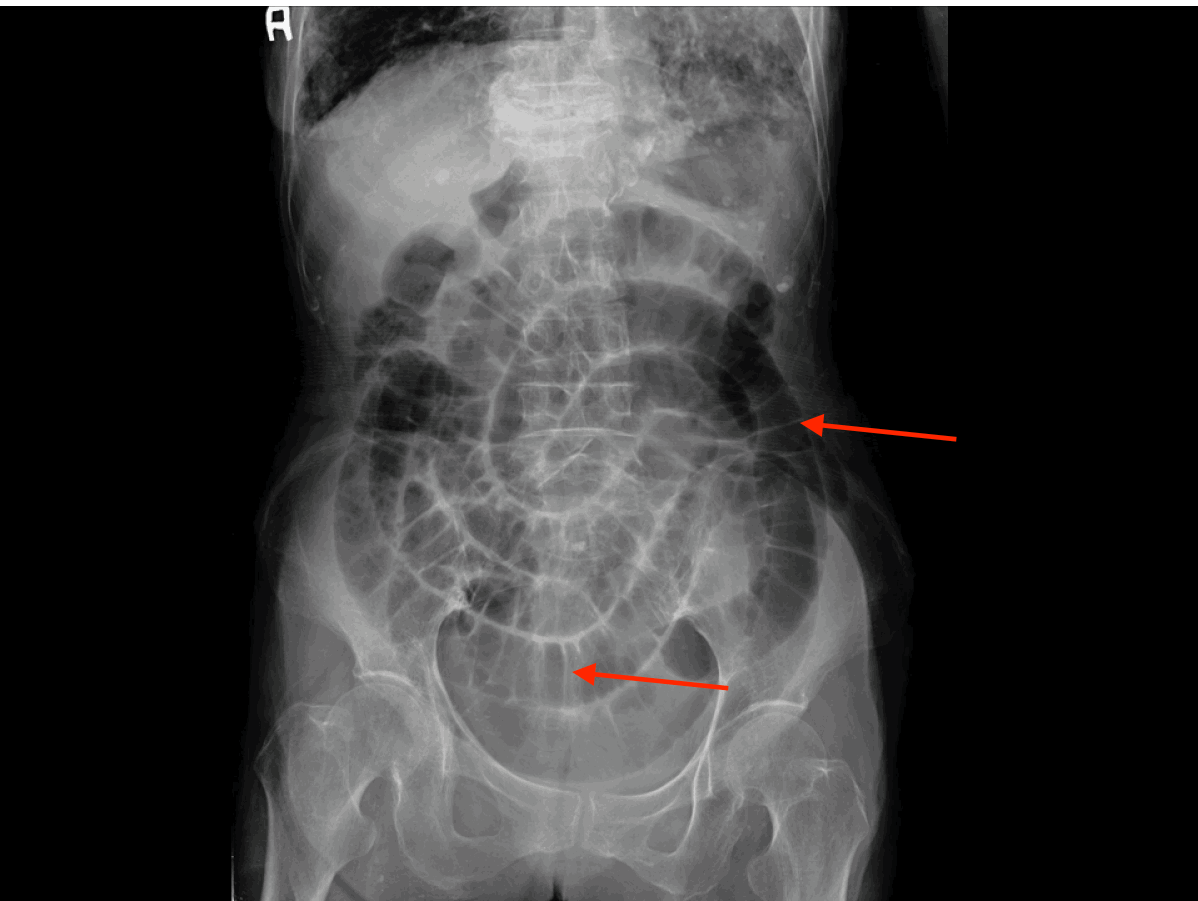

Ileus and small bowel obstruction Cancer Therapy Advisor Constipated Bowel X Ray When a hard stool mass becomes stuck in your colon due to prolonged constipation, it’s known as fecal impaction. When your body is working. Fecal impaction is the result of constant constipation when poop is stuck inside of your rectum. Fecal impaction is most commonly a complication of chronic or severe constipation where inspissated hard feces accumulates in the distal.. Constipated Bowel X Ray.

Abdominal Xray showing distended loops of bowel before admission... Download Scientific Diagram Constipated Bowel X Ray Fecal impaction is the result of constant constipation when poop is stuck inside of your rectum. When a hard stool mass becomes stuck in your colon due to prolonged constipation, it’s known as fecal impaction. You swallow capsules with the. When your body is working. Symptoms include pain or difficulty. Fecal impaction is most commonly a complication of chronic or. Constipated Bowel X Ray.